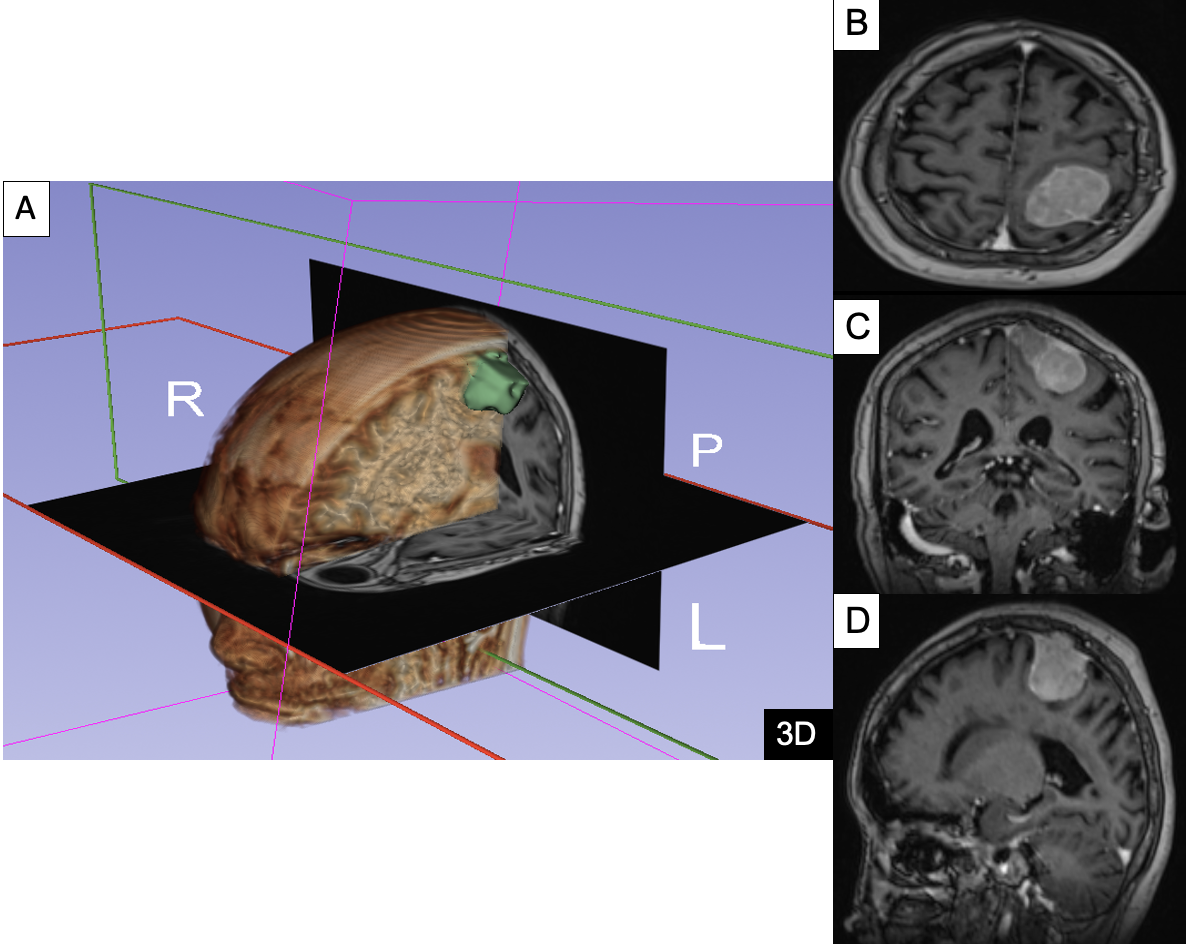

• Các thiết bị chẩn đoán hình ảnh hiện đại: CT scan, MRI, máy siêu âm 5 chiều